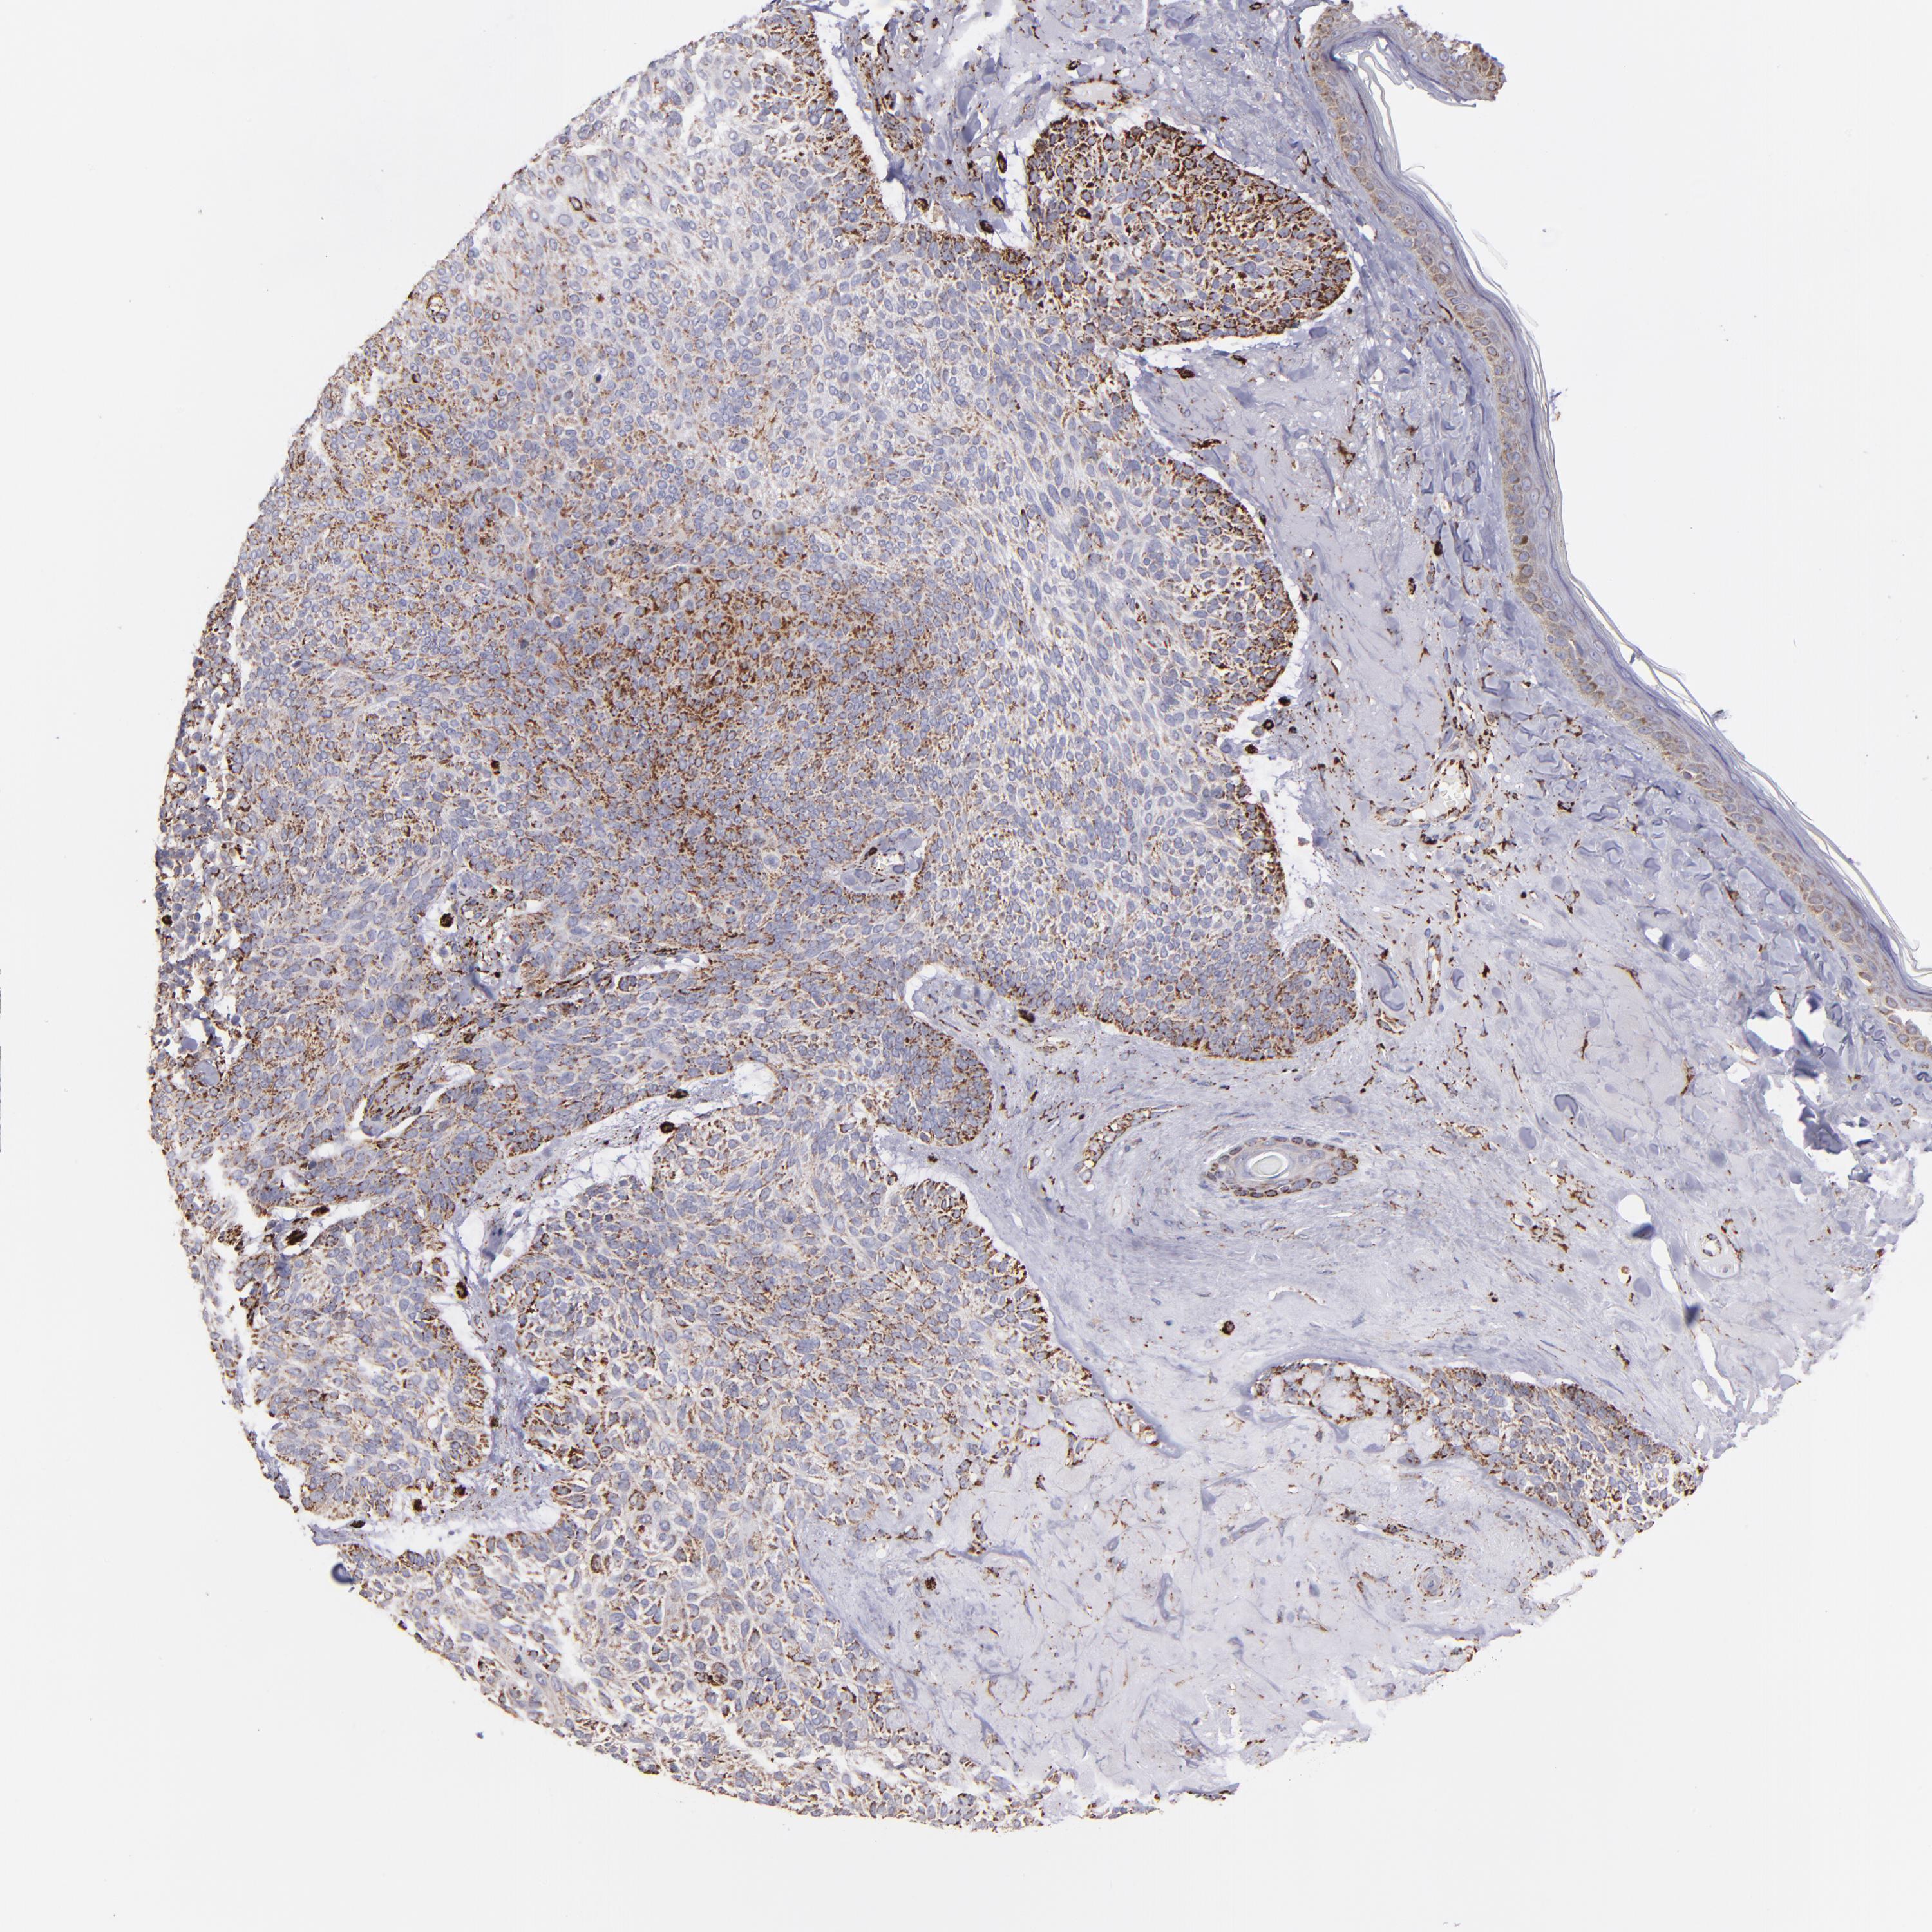

CANCER SKIN CANCER Show tissue menu

Basal cell and squamous cell cancer

SKIN CANCER - Protein expressioni

A mouse-over function shows sample information and annotation data. Click on an image to view it in a full screen mode. Samples can be filtered based on level of antibody staining by selecting one or several of the following categories: high, medium, low and not detected. The assay and annotation is described here.

Each image is clickable and will lead to virtual microscopy that enables deeper exploration of all samples and also displays staining intensity scores, fraction scores and subcellular localization as well as patient and tissue information for each sample.

Antibody HPA002328

Squamous cell carcinoma, NOS

Basal cell carcinoma

Squamous cell carcinoma, metastatic, NOS